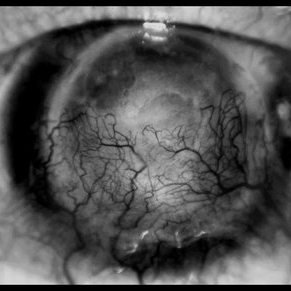

CORNEA

64-year-old patient, with vision loss more than 10 years after having suffered blunt trauma with ocular perforation.

Photographer: JEFFERSON R SOUSA - Study Center and Ophthalmological Research Dr. Andre M V Gomes, Institute Dr. Suel Abujamra São Paulo-Brazil

Imaging device: Topcon TRC-50 DX, Imaginet 5.0, angle de 20 graus. Flash 36.

Condition/keywords: 20 degrees, central opacity of cornea, corneal edema, neovascularization (NV)